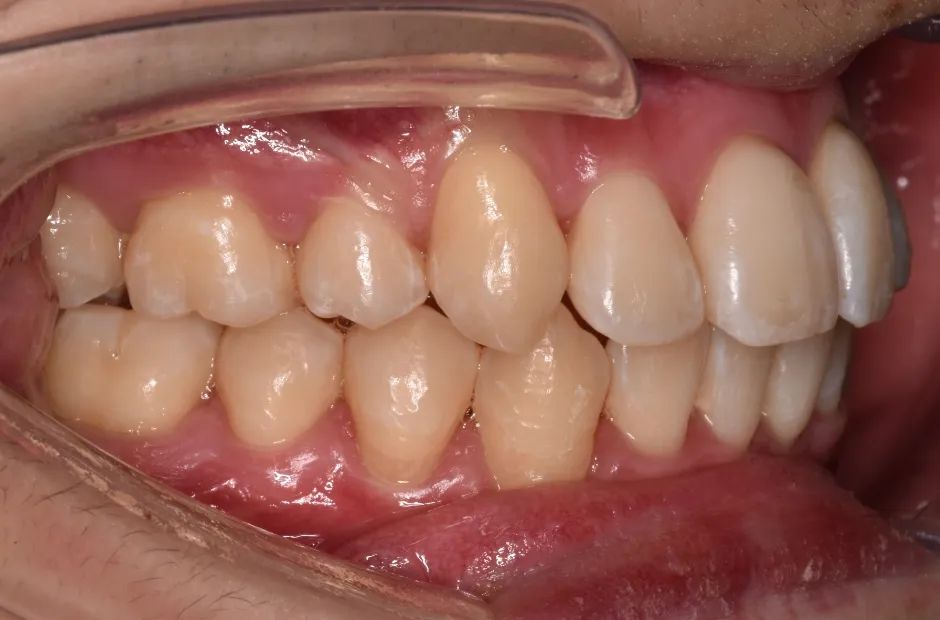

治療症例

ブラケット矯正

前歯部反対咬合

| 診断名・主訴 | 前歯部反対咬合 |

|---|---|

| 年齢・性別 | 14歳・男性 |

| 治療期間・回数 | 1年2か月 |

| 治療に用いた主な装置 | ブラケット矯正 |

| 抜歯部位 | なし |

| 治療費 | 60万円(税抜) |

| リスク・副作用 | 装置による違和感・疼痛・歯肉退縮・歯根吸収・虫歯のリスクなど |

治療前

治療後